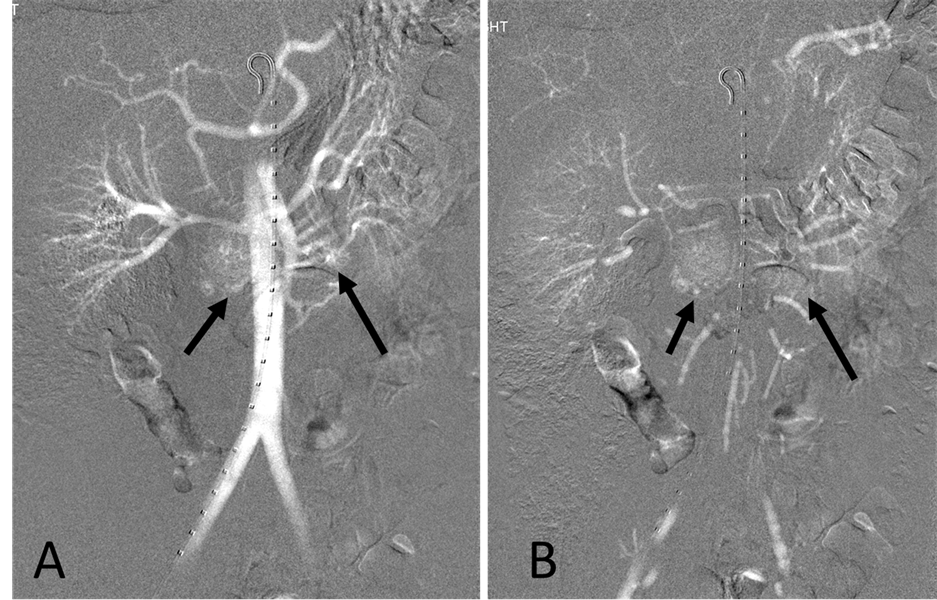

With the patient under general anesthesia, a 5-Fr Omni Flush catheter (Angio Dynamics, Queensbury, NY, USA) was placed in the aorta above the celiac axis from a percutaneous retrograde transfemoral arterial approach, and aortograms were performed, first with 30 cc of CO2 and then in the anterior-posterior (AP) and left anterior-oblique (LAO) projections with Visipaque (GE Healthcare, Cork, Ireland, UK). During each of the runs, there was a moderate increase in blood pressure from baseline systolic pressures of 120 s to 145 - 150 s, lasting 5 minutes, accompanied by bradycardia and transient arrhythmia. A nitroglycerin drip was started; however, the patient did not require any alpha or beta blockers. Next, a 5-Fr shepherd hook catheter (Angio Dynamics, Queensbury, NY, USA) was positioned and digital subtraction angiography (DSA) was performed, sequentially, in the right and left renal arteries, superior mesenteric artery, and finally the celiac axis. The aortograms revealed two vascular retroperitoneal tumors to the right and left of the aorta, at the level of L1-2, measuring 22 mm × 27 mm and 26 mm × 27 mm, respectively (Figure 2(A) and Figure 2(B)). The right retroperitoneal mass was located posteroinferior to the right renal artery and posterior to the inferior vena cava (IVC). The left retroperitoneal mass was located between the left main renal artery and the inferior accessory renal artery. The inferior accessory renal artery supplying the lower pole of left kidney showed diffuse narrowing due to either compression or catecholamine release by the tumor (Figure 3(A) and Figure 3(B)). Subsequently, bilateral renal arteriograms were performed without a hypertensive response to the injection of contrast material. The right main renal artery was displaced by the tumor with mild arterial narrowing (Figure 4(A) and Figure 4(B)). Left renal arteriogram showed a patent main renal artery with a circumaortic renal vein (Figure 5(A) and Figure 5(B)).

Figure 3. (A) Aortogram with iodinated contrast medium in left anterior oblique projection. The tumors show fine neovascularity. The inferior accessory renal artery (arrow) abutting the inferior margin of the tumor shows diffuse narrowing; (B) Capillary phase. There is irregular, increased contrast accumulation throughout the tumors (arrows).